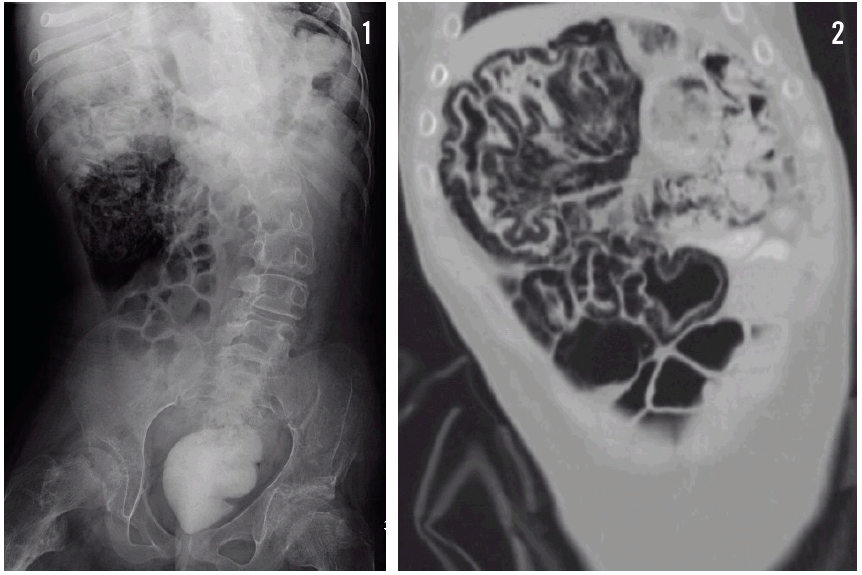

Venkedesh Raju, MD; Zahangir Khaled, MD; Eric Bugaieski, MD; Shoba Theivanayagam, MD

A 9-year-old girl, newly diagnosed with Crohn disease, had had a good response with resolution of symptoms after treatment with prednisone and mesalamine.